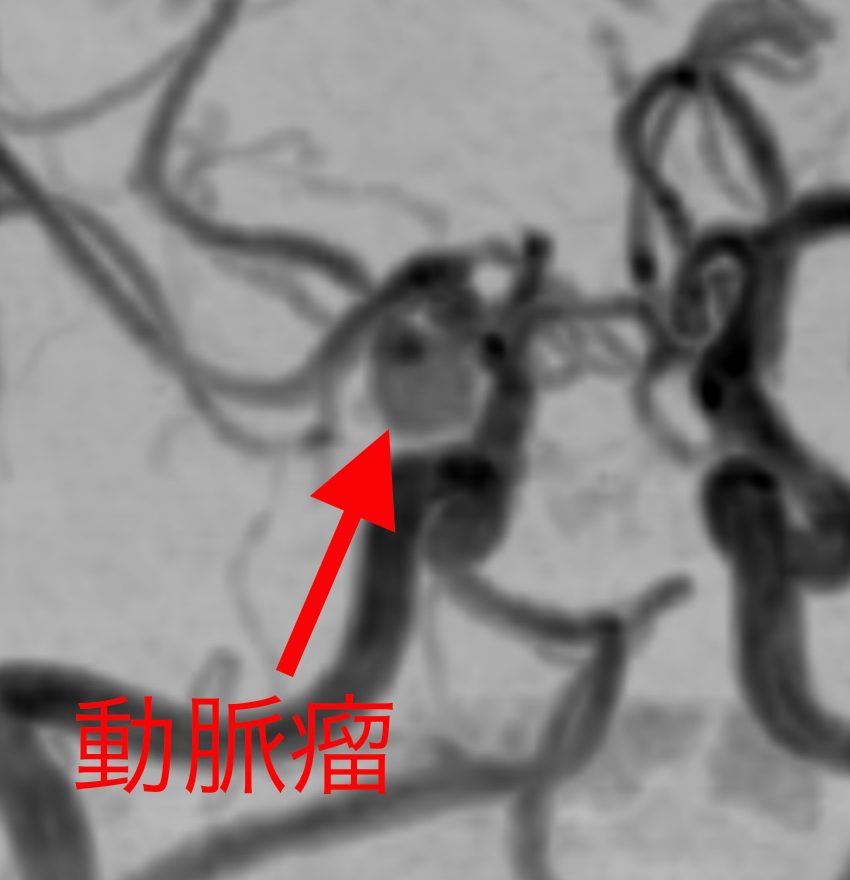

もし、脳卒中になってしまったら、残念ながら現在の医療では完全に治す事はできません。しかし、脳卒中は発病する前に予測して予防する事ができます。たとえば、くも膜下出血は脳内の動脈瘤が破裂して起こる病気ですが、MRI検査で破裂する前の動脈瘤を発見する事が可能です。だからこそ、健康だと思っている今、MRI検査で予防につなげる事が大切です。

未破裂脳動脈瘤

動脈瘤があるだけでは無症状です。症状が出てからでは遅いので、大きい場合には手術を行います。